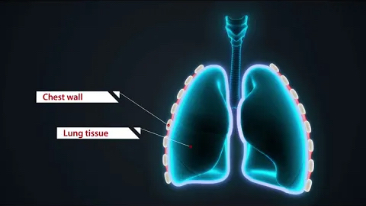

Since the company was founded, Mindray has been continuously exploring new ways to improve diagnostic confidence. Powered by the most revolutionary ZONE Sonography? Technology, Resona 7ŌĆÖs new ZST+ platform brings ultrasound image quality to a higher level by zone acquisition and channel data processing.

As well as the premium level image quality, Resona 7 also enhances clinical research capabilities with the revolutionary V Flow for vascular hemodynamic evaluation, and the most intelligent plane acquisition from 3D datasets for fetal CNS diagnosis. Combining the most intuitive gesture-based multi-touch operation and all the essential clinical features, Resona 7 is truly leading new waves in ultrasound innovation.